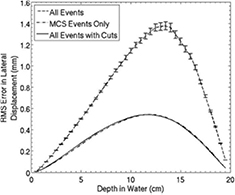

Not surprisingly, the tracking uncertainties are small compared with the spatial uncertainties that result from the proton passage through a typical phantom, which for the purpose of this discussion we assume to be a cylinder of water with a diameter of 200 mm. The front and rear tracks both contribute to the prediction of a proton's path through the phantom. Consider, for example, trying to predict the location of the proton's path at the phantom center for a 200 MeV proton passing more-or-less along a diameter. From equation (30.19) in [45], the positional uncertainty at the phantom center due to multiple scattering, considering just the front track projection, will be  , but that is with the optimistic and incorrect assumption that the energy of the proton remains constant at 200 MeV, whereas it is expected to decrease to 150 MeV by the time it reaches the center of the phantom. In fact, the rear tracker tends to have significantly less predictive power than the front tracker, because the proton kinetic energy is reduced by the time it exits the phantom. Therefore, the point on the path with the largest predictive uncertainty lies beyond the center, as can be seen in figure 3, where the maximum error on the prediction of the path of a 200 MeV proton passing through 200 mm of water, calculated from both front and rear track vectors, is between

, but that is with the optimistic and incorrect assumption that the energy of the proton remains constant at 200 MeV, whereas it is expected to decrease to 150 MeV by the time it reaches the center of the phantom. In fact, the rear tracker tends to have significantly less predictive power than the front tracker, because the proton kinetic energy is reduced by the time it exits the phantom. Therefore, the point on the path with the largest predictive uncertainty lies beyond the center, as can be seen in figure 3, where the maximum error on the prediction of the path of a 200 MeV proton passing through 200 mm of water, calculated from both front and rear track vectors, is between  mm and

mm and  mm, and occurs about 115 mm from the phantom entrance.

mm, and occurs about 115 mm from the phantom entrance.

Figure 3. The Monte Carlo predicted deviation of the most likely path (MLP) of a proton from its actual trajectory, for 200 MeV protons passing through 200 mm of water. From [76] John Wiley & Sons. © 2008 American Association of Physicists in Medicine. Most large deviations due to simulated nuclear interactions and hard scattering were easily eliminated by cutting out events with large exit angles, leaving events affected mainly by multiple Coulomb scattering.